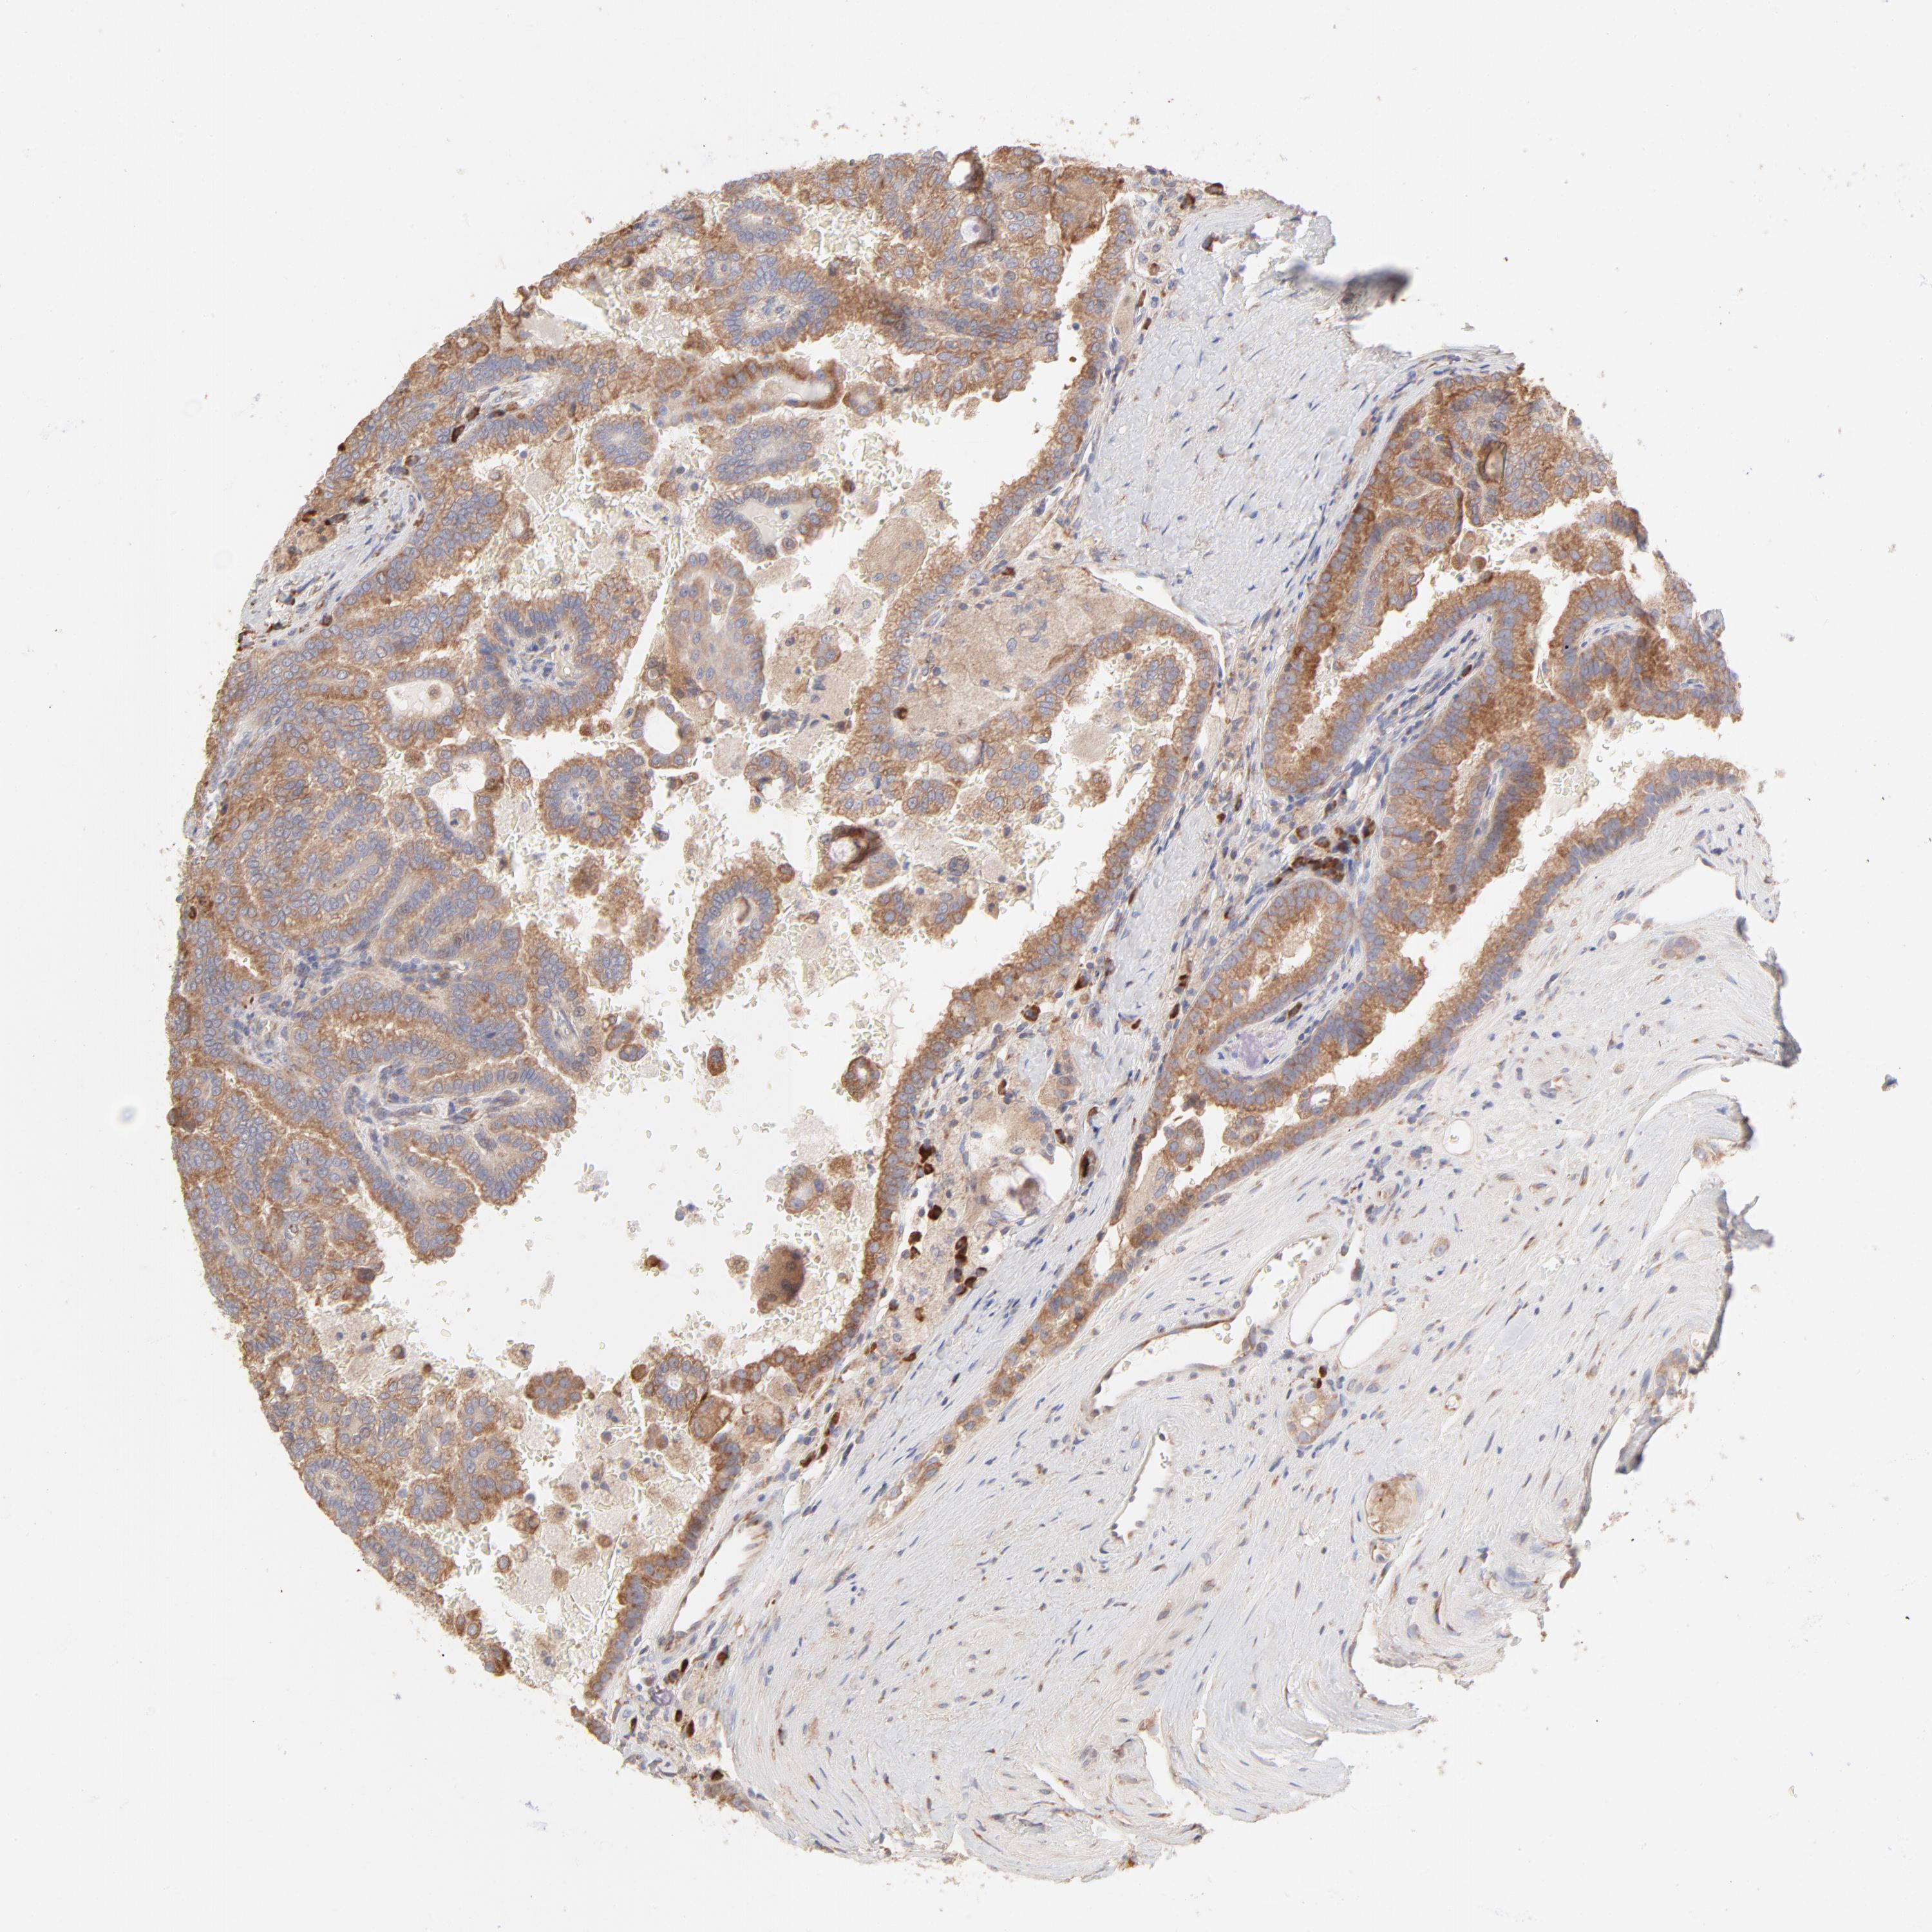

KIDNEY RENAL CLEAR CELL CARCINOMA (VALIDATION) - Interactive survival scatter ploti

The Survival Scatter plot shows the clinical status (i.e. dead or alive) for all individuals in the patient cohort, based on the same data that underlies the corresponding Kaplan-Meier plots. Patients that are alive at last time for follow-up are shown in blue and patients who have died during the study are shown in red.

The x-axis shows the expression levels (FPKM) of the investigated gene in the tumor tissue at the time of diagnosis. The y-axis shows the follow-up time after diagnosis (years). Both axes are complimented with kernel density curves demonstrating the data density over the axes. The top density plot shows the expression levels (FPKM) distribution among dead (red) and alive patients (blue). The right density plot shows the data density of the survived years of dead patients with high and low expression levels respectively, stratified using the cutoff indicated by the vertical dashed line through the Survival Scatter plot. This cutoff is automatically defined based on the FPKM cutoff that minimizes the p-score. The cutoff can be changed by dragging the vertical line or by entering a cutoff value in the square labeled "Current cut-off".

Under the Survival Scatter plot the p-score landscape (black curve; left axis) is shown together with dead median separation (red curve; right axis). Dead median separation is the difference in median mRNA expression between patients who have died with high and low expression, respectively. It is calculated as follows: median FPKM expression of dead patients with high expression - median FPKM expression of dead patients with low expression. This is intended to aid the user in visually exploring custom cutoffs and the associated p-scores and dead median separation.

Individual patient data is displayed and can be filtered by clicking on one or more of the category buttons on the top of the page. Categories describing expression level and patient information include: high, low, alive, dead, female, male and tumor stages. The scale of the x-axis can be toggled between linear and log-scale by clicking on the "x log" button. Mouse-over function shows TCGA ID, patient information and mRNA expression (FPKM) for each patient.

& Survival analysisi

Kaplan-Meier plots summarize results from analysis of correlation between mRNA expression level and patient survival. Patients were divided based on level of expression into one of the two groups "low" (under cut off) or "high" (over cut off). X-axis shows time for survival (years) and y-axis shows the probability of survival, where 1.0 corresponds to 100 percent.

RPS21 is not prognostic in Kidney Renal Clear Cell Carcinoma (validation)

Best expression cut offi

Based on the FPKM value of each gene, patients were classified into two groups and association between prognosis (survival) and gene expression (FPKM) was examined. The best expression cut-off refers the FPKM value that yields maximal difference with regard to survival between the two groups at the lowest log-rank P-value. Best expression cut-off was selected based on survival analysis .

When clicking on this number, the vertical dashed line indicating cut-off, the interactive survival plot, and the Kaplan-Meier curve will be adjusted to show results based on the best expression cut-off.

: 2251.72

P scorei

Log-rank P value for Kaplan-Meier plot showing results from analysis of correlation between mRNA expression level and patient survival.

N/A

Average pTPM 1868.6

Number of samples 100